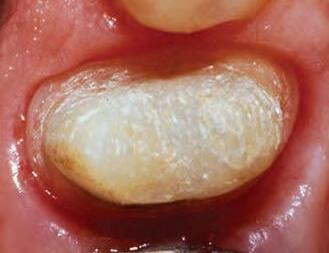

1. Well-healed tissue 2 weeks post-op.

Note: Perfect sulcular fluid control is mandatory if bonding and luting is adjacent to gingival sulcus.1

MICROLEAKAGE

PROVISIONAL REMOVED STAINING

2. Upon removing some of the composite, the extent of leakage is more evident. Contamination has occurred, therefore compromising the seal. Hemostatic, blood, sulcular fluid, saliva, and byproducts from anerobic bacteria can be sources of contamination. Retreatment is necessary.

1. For restorations, Astingedent™ X hemostatic and Ultrapak cord are ideal for controlling blood and sulcular fluids and can also protect tissue from burs. Use a firm air/water spray to remove excess hemostatic solution.

1. Packing Ultrapak cord quickly displaces tissues and improves access for indirect veneer luting.